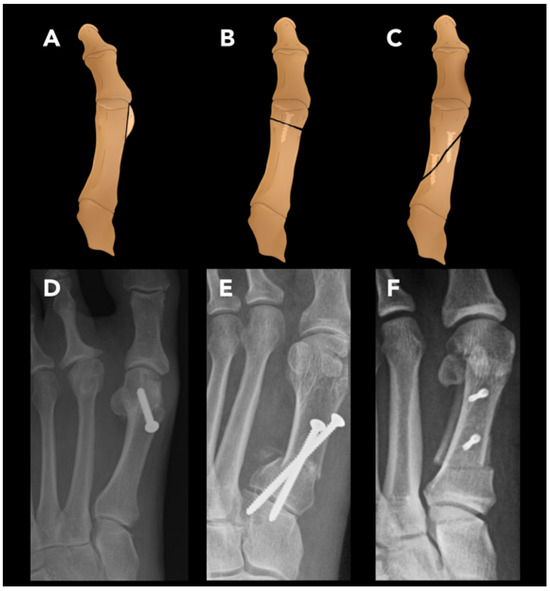

2.3.4. Hallux Valgus Osteotomy